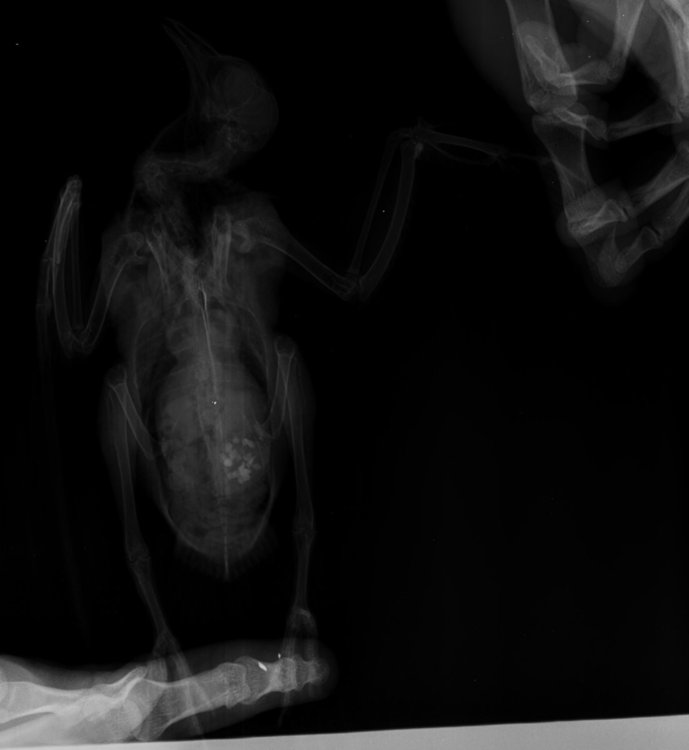

Duch Опубликовано 30 марта, 2020 #1 Опубликовано 30 марта, 2020 Здравствуйте! Приютился у нашего офиса, примерно 2 месяца назад, голубь и никак не улетал. Сделали вывод, что проблемы с крылом, т.к. левое он странно прижимал к себе. Положили в коробку, налили воды, насыпали гречи. Отогрелся спустя неделю, но крыло так и прижимал к себе. Предположили перелом крыла. Отвезли к орнитологу, сделали снимок (прикрепили к топику). Общий осмотр весьма позитивен, на снимке перелома нет. Выписали уколы витаминов и обезболивающих. Прокололи курс недели 2 назад - без изменений. На данный момент крыло так и прижимает к себе, огрызается, когда ему сыпят корм или доливают воды. Иногда клюёт и бьёт крылом, но только правым. Пока ждём выхода орнитолога из очередного отпуска, стараемся за ним ухаживать. В прошлую пятницу насыпали ему корм и подлили воды в плошку. Приехал в субботу вечером, дабы проведать. В итоге, он за целый день ничего не съел и не пил. На мои касания никак не реагировал: вжался в себя и стоял напуганный. Взял на руки, дабы осмотреть, как из под него показалась муха/слепень и тут же скрылась. Погуглил - оказывается, это - кровососки. Купил в ветеринарном отделе ампулу с препаратом, которую следовало разбавить 1,6л воды. Опрыскал её под крыльями, напоил водой из шприца и оставил так на день. Судя по корму, начал немного есть и пить. Кормплю гречкой, рисом и разваренным пшеном из шприца. Но сегодня обратил внимание, что он, когда клюёт сухой корм, как бы, промахивается и не может заглотить крупинку - гречка отскакивает в сторону и пытается еще раз захватить другую, но результат тот же. При всем при это, он четко видит мою руку и реагирует на неё соответствующим образом, т.е. слепоты нет Очень рассчитываю на вашу помощь! Ранее не имел опыта ухода за птицами

Виктория М. Опубликовано 30 марта, 2020 #2 Опубликовано 30 марта, 2020 (изменено) Здравствуйте. Нужен точный вес голубя. Помет желательно на листе белой бумаги. Проверьте нет ли наростов во рту , а также неприятныого запаха (кислого, тухлого). Кормить; 1 столовая ложка с горочкой 2 раза в день. Помимо гречи добавьте перловую крупу ,чечевицу или колотый горошек, пшеницу, овес без шелухи. Рис лучше уберите его можно но совсем немного. С каким препаратом ампула была? Все что обнаружил врач и все его назначения нужно выложить сюда на сайт, чтобы понимать чем вы лечили птицу. Какие витамины кололи какой курс и тд. Чтобы голубь начал нормально клевать зерно, в человеческой аптеке купите ноотропил таб или пирацетам . В вет аптеке нужно приобрести Фоспренил. Мух кровососок если вдруг еще обнаружите хорошо в тазике с водой вылавливать. Сажаете птицу в тазик с теплой водой, чтобы только голова на поверхности была, придерживаете аккуратно и так мин 10 -15 сидите с ним они начнут всплывать. Ваша задача не дать им вылететь из воды - передавить. Какое крыло он прижимает если смотреть на ренген? Изменено 30 марта, 2020 пользователем Виктория М.

маленький принц Опубликовано 1 апреля, 2020 #5 Опубликовано 1 апреля, 2020 (изменено) а можно рентген более крупный а не мелкий? у Вас на этой мелкой картинке трудно разглядеть подробности ВНОВЬ ЛЕТАТЬ и Здоровья Вашему голубю! чтобы узнавать новые ответы в Вашей теме нажмите пожалуйста наверху Вашей темы "подписаться" Изменено 1 апреля, 2020 пользователем маленький принц

Duch Опубликовано 1 апреля, 2020 Автор #6 Опубликовано 1 апреля, 2020 31.03.2020 в 01:36, Виктория М. сказал: Здравствуйте. Нужен точный вес голубя. Помет желательно на листе белой бумаги. Проверьте нет ли наростов во рту , а также неприятныого запаха (кислого, тухлого). Кормить; 1 столовая ложка с горочкой 2 раза в день. Помимо гречи добавьте перловую крупу ,чечевицу или колотый горошек, пшеницу, овес без шелухи. Рис лучше уберите его можно но совсем немного. С каким препаратом ампула была? Все что обнаружил врач и все его назначения нужно выложить сюда на сайт, чтобы понимать чем вы лечили птицу. Какие витамины кололи какой курс и тд. Чтобы голубь начал нормально клевать зерно, в человеческой аптеке купите ноотропил таб или пирацетам . В вет аптеке нужно приобрести Фоспренил. Мух кровососок если вдруг еще обнаружите хорошо в тазике с водой вылавливать. Сажаете птицу в тазик с теплой водой, чтобы только голова на поверхности была, придерживаете аккуратно и так мин 10 -15 сидите с ним они начнут всплывать. Ваша задача не дать им вылететь из воды - передавить. Какое крыло он прижимает если смотреть на ренген? Прикрепил назначение врача Во рту ничего подозрительного, как и в запахе. Может прозвучать неоднозначно, но он в вцелом, приятно пахнет) Ампула, которую разбавил в воде и опрыскивал 2 дня голубя под перья ( на тело) - "Дельцид" В воду окунали, правда держали минут 5. Ничего не всплыло и мы аккуратно его сушили феном, т.к. он сильно замёрз. Потом на форуме прочел, что насильное купание голубей недопустимо Глядя на рентген то, что раскрыто, т.е. правое. Делали снимок лёжа на спине, соответственно, по факту, это левое крыло

OFA Опубликовано 2 апреля, 2020 #25 Опубликовано 2 апреля, 2020 @Duch сама доктор смотрела рентген птицы? Что-то сказала? Нужно позвать нашего форумского доктора @Zosia посмотреть рентген. Может так разложена птица, но мне что-то кажется, что плечевой сустав не в порядке, но лучше пусть Зося посмотрит. Птица взрослая, клевать умеет, значит проблема или с жкт, или вертячка в такой форме.

маленький принц Опубликовано 2 апреля, 2020 #26 Опубликовано 2 апреля, 2020 @OFA рентген - в виде мелкой картинки просил автора залить рентген покрупнее

маленький принц Опубликовано 2 апреля, 2020 #30 Опубликовано 2 апреля, 2020 (изменено) @Duch вот рентген Вашего пациента Изменено 2 апреля, 2020 пользователем маленький принц

маленький принц Опубликовано 3 апреля, 2020 #33 Опубликовано 3 апреля, 2020 12 часов назад, Duch сказал: ну да, разве не его я прикрепил в прошлом сообщении? оно почему-то ужалось до мелких размеров если пойти по ссылке https://www.mybirds.ru/forums/uploads/monthly_2020_03/1SXcxYu_0rk.jpg.d7c82758490ddb04a65127b887286e57.jpg.28c0e1b9697a84b0cce71b1ee39e8254.jpg и открыть то видно что оно очень мелкое потому я скачав Ваш архив перезалил фото и увидев что оно ограничено по размерам дважды обрезав перезалил ещё раз